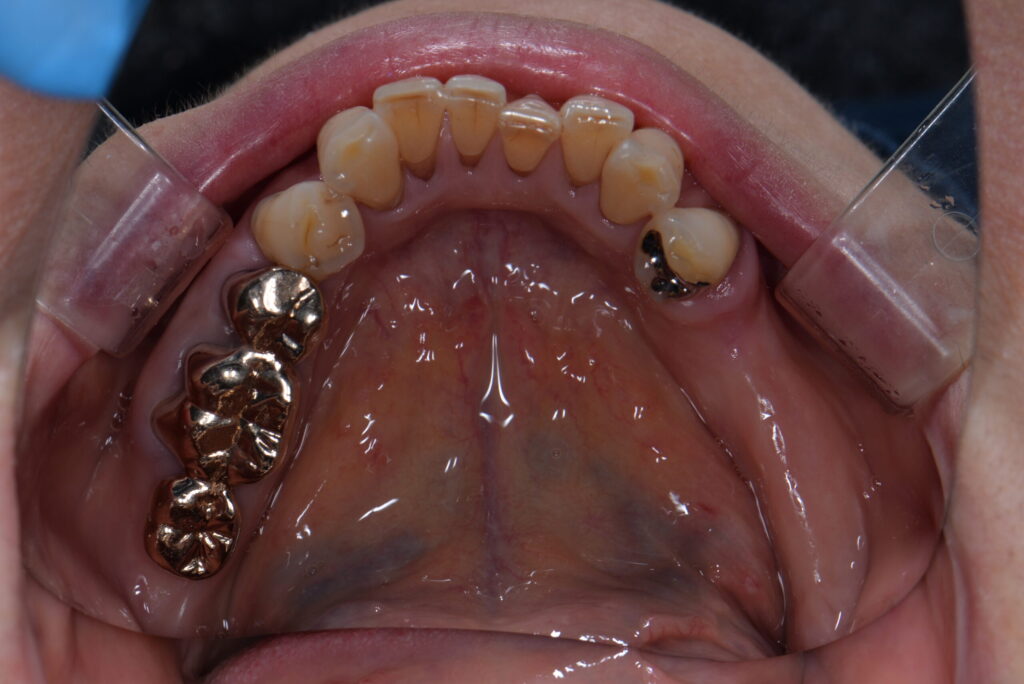

術前